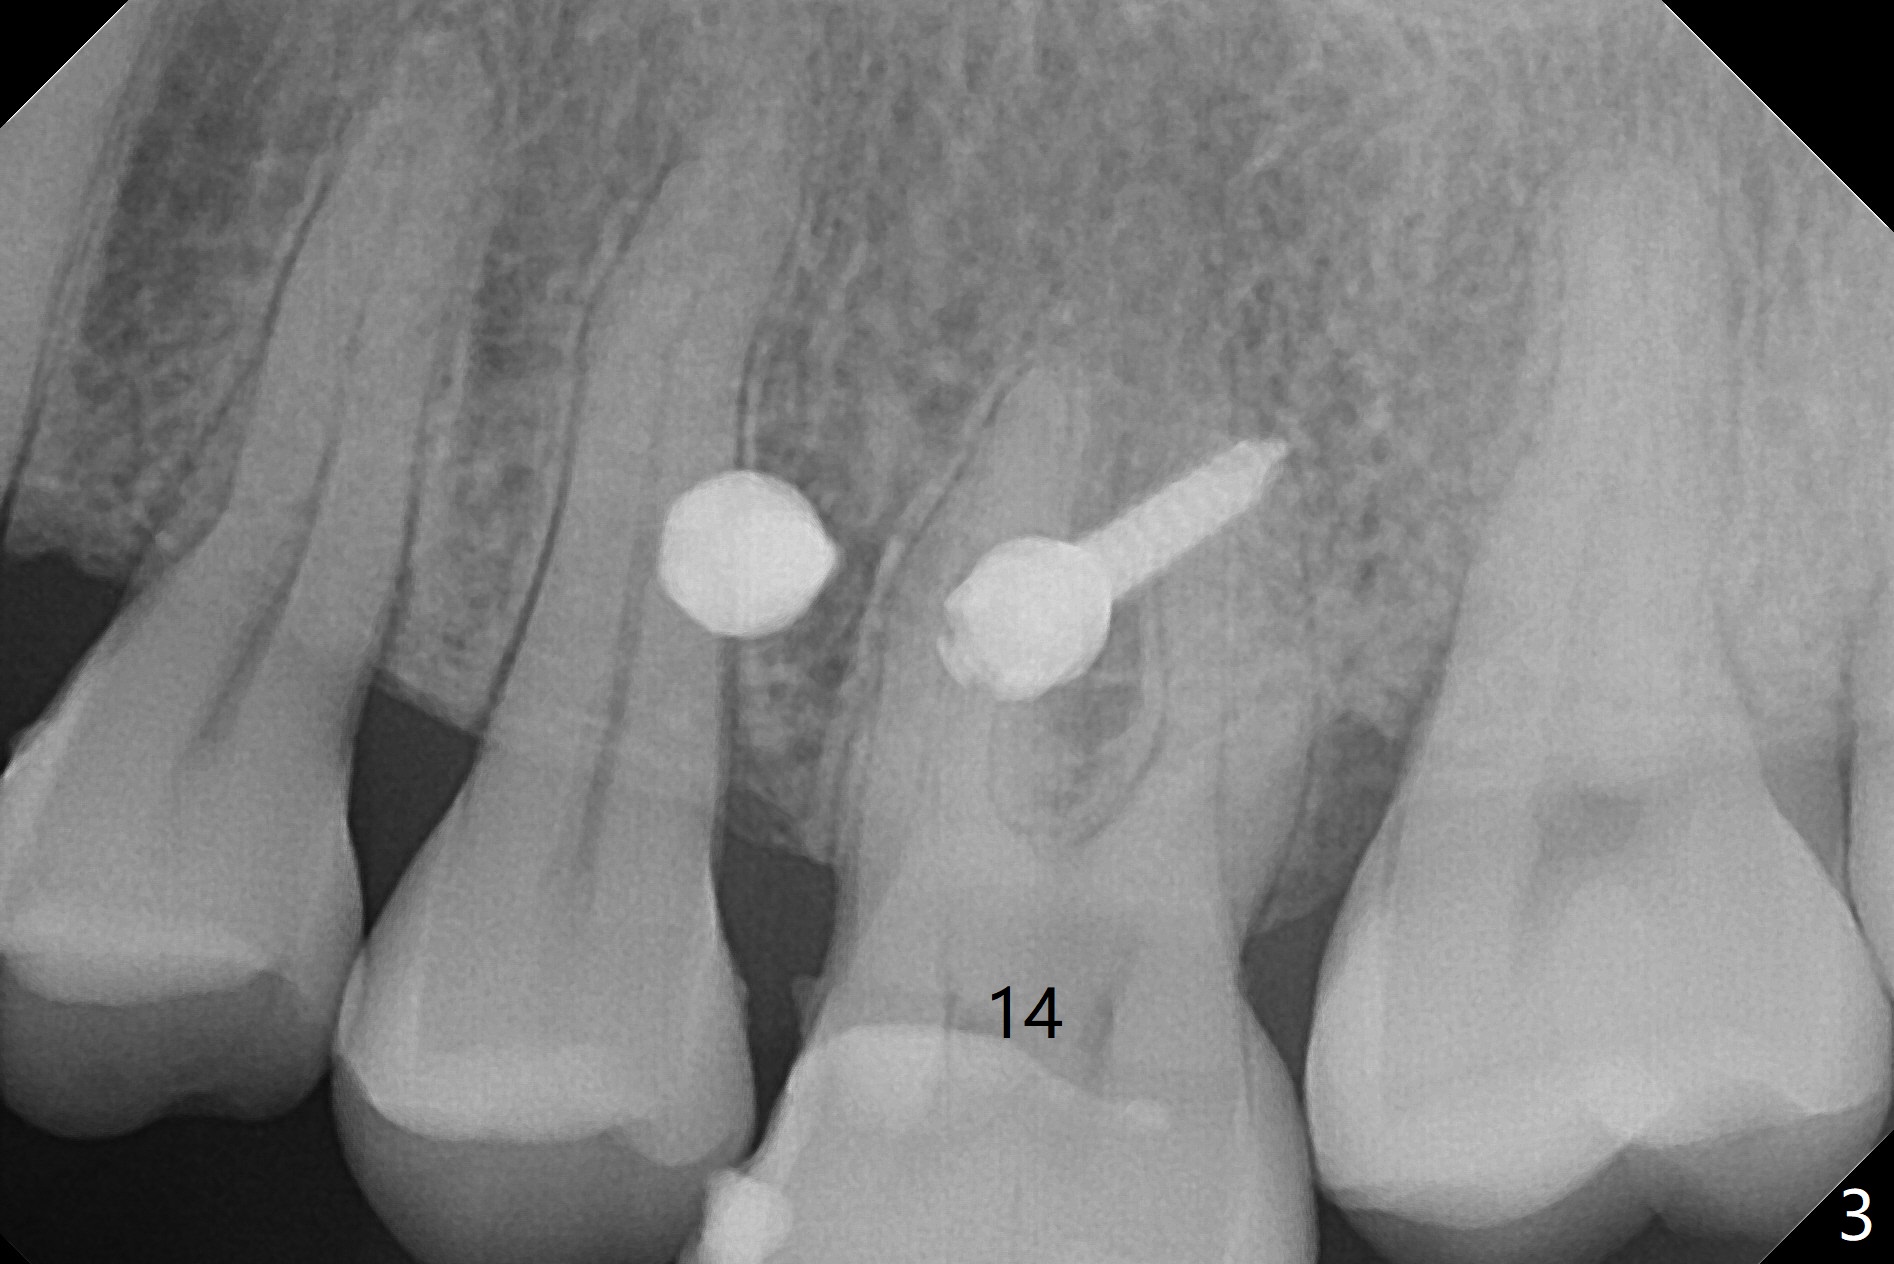

Fourteen days prior to implantation at #19 to replace a flipper (Fig.2), two minimplants are placed to intrude the supraerupted opposing tooth (#14, Fig.1). After use of minimal amount of local anesthetic (to keep proprioceptive in case root surface violation), the miniimplants are inserted ~ half of the length initially (Fig.3,4). The mesiobuccal (MB) one seems to be better positioned than the distopalatal (DP) one. When the implants are completely seated (Fig.5,6), three of PAs are taken, which suggests contact of the MB implant to the MB root of the tooth #14 (Fig.7 arrow). Immediately postop CT confirms approximation of MB and DP implants to the MB and P roots, respectively (Fig.8,9). The trajectory of these implants remain unchanged. Twelve days postop, the patient returns, uncomfortable with the palatal implant. After deep placement to bury the cuff (Fig.6) without local anesthesia (bone having no innervation), the patient feels better.